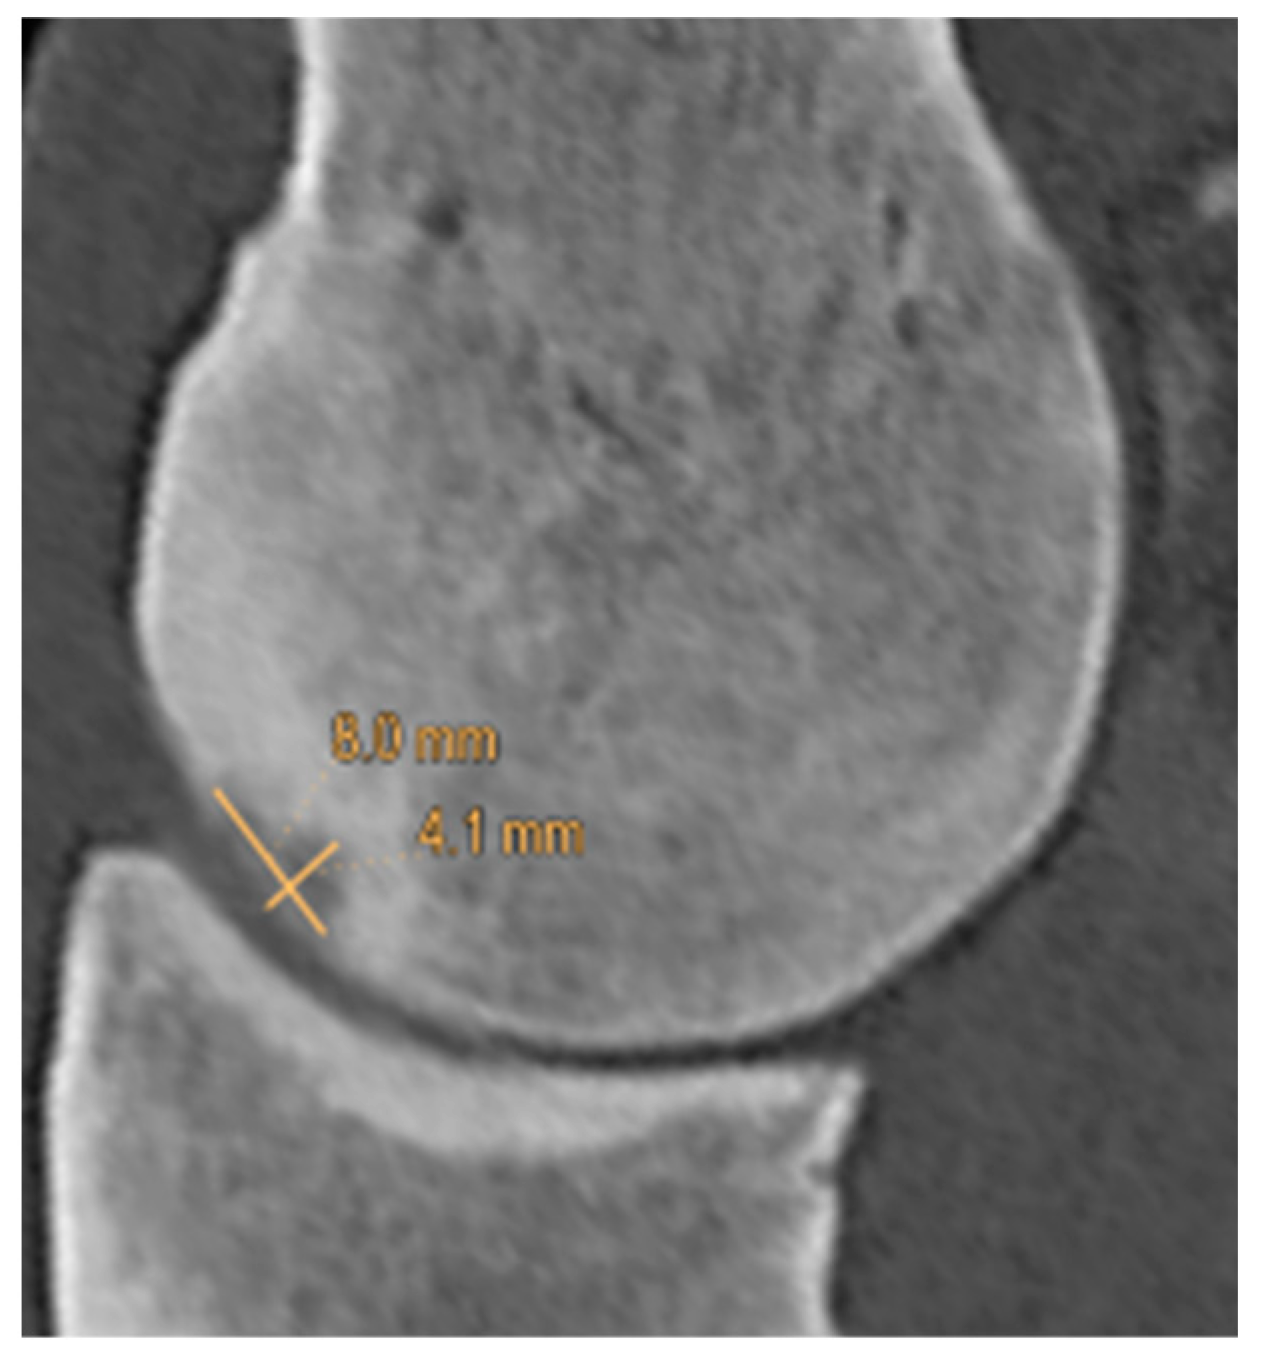

| Proximodistal extent (mm) | Median | 5.3 | 4.3 | 4.0 |

| 95% CI | 4.3–11.7 | 3.6–12.3 | 2.9–14.5 | |

| Dorsopalmar extent (mm) | Median | 2.1 | 1.7 | 2.1 |

| 95% CI | 0.7–1.9 | 0.5–1.6 | 0.5–2.5 | |